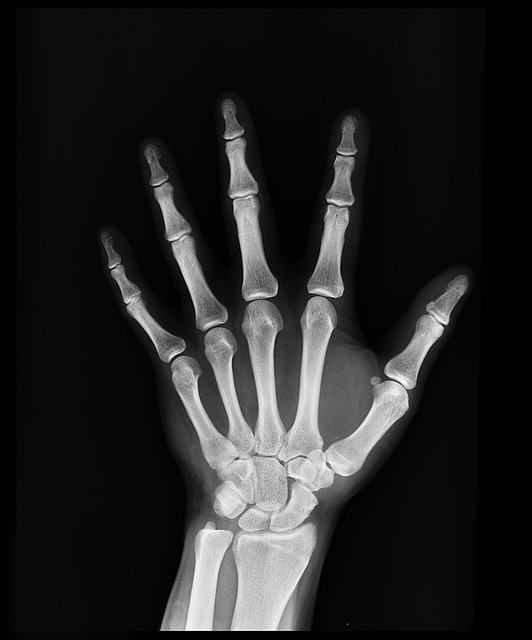

• 방사선 검사 : 엑스레이, MRI 등을 통해 관절 손상 여부 확인 가능